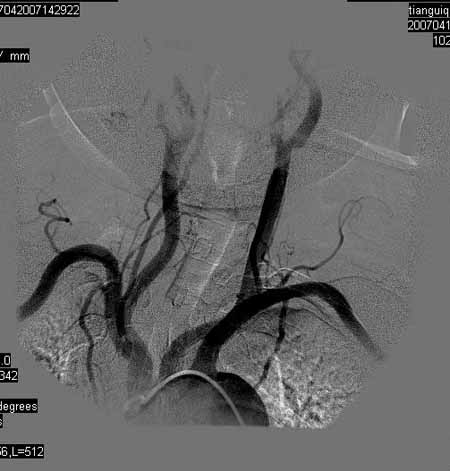

标题: DSA0093:脑血管造影

女,63岁,左侧额、枕叶脑梗塞。

右肾动脉及左颈内动脉起始部狭窄(考虑动脉硬化引起的),大脑中动脉分支减少.

右肾动脉及左颈内动脉起始部狭窄(考虑动脉硬化引起的),